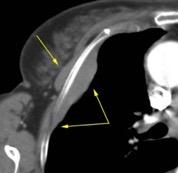

Caída bicicleta. Separación acromioclavicular. Fracturas costales múltiples. Contusión pulmonar basal basal con evolución a hematoma